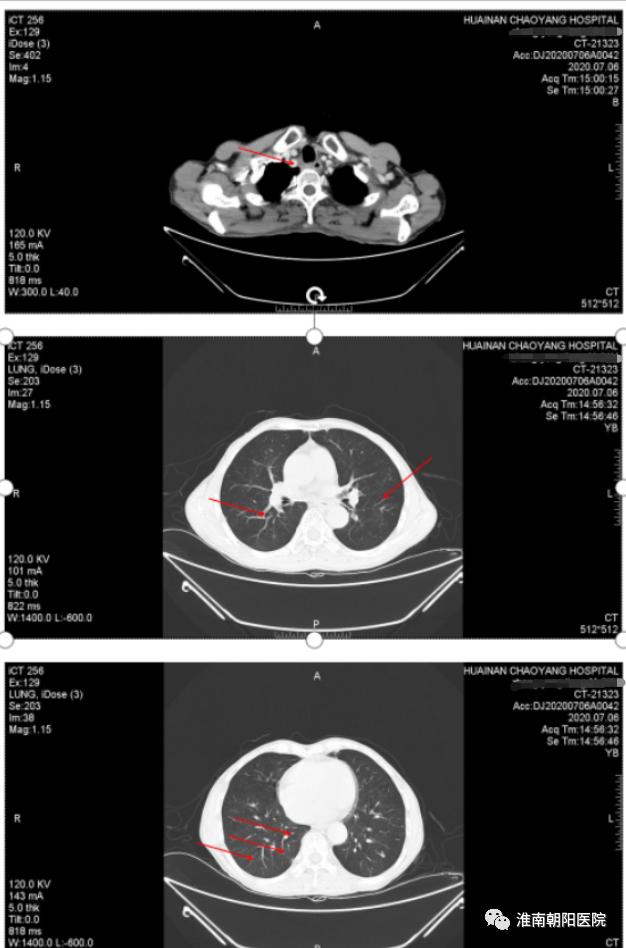

经过淮南朝阳医院肿瘤中心医护人员耐心而温情的安慰后,张大爷决定继续坚持与病魔抗争,之后的 2 个月他又勇敢地接受了 2 周期化疗。但晚期复发性食管癌传统治疗并没有给我们带来惊喜的疗效,张大爷再次出现了明显的进食哽阻感、食欲下降、呕吐等不适症状,身体越来越消瘦, 在今年 3 月份复查的时候两肺多发转移较前进展了,并出现了新的转移灶(右侧胸廓入口处)。

(图为新的转移灶)

(红色箭头提示肺内的病灶明显增大了)